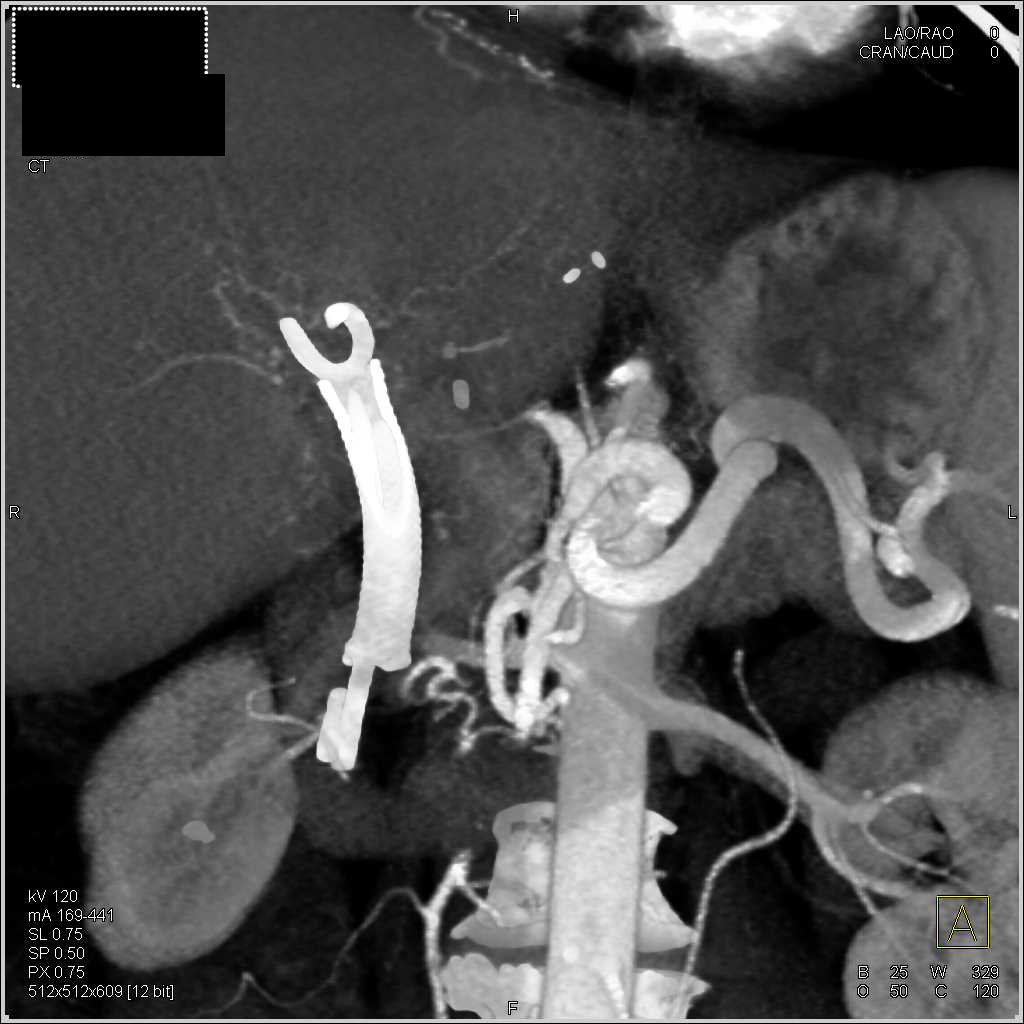

Unusual Case with Active Bleeding into the Gallbladder